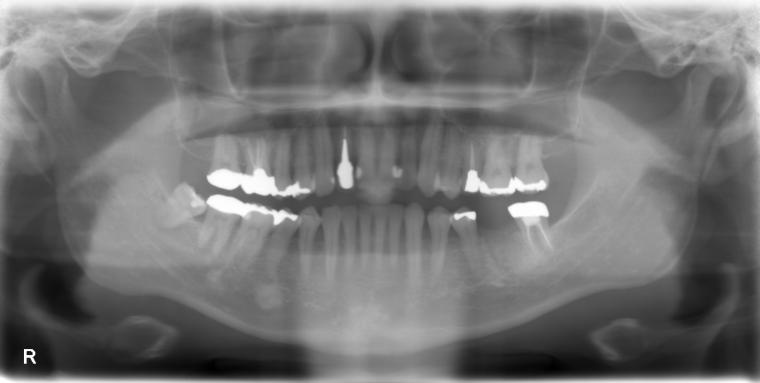

AFTER

44歳男性

/下顎1本欠損/インプラント埋込手術

他院で左下第一大臼歯を治療していましたが、治療を中断してしまい、状態が悪化、抜歯になった患者さんです。

インプラントでの治療を希望されて当院へご来院されました。

現在は定期検診で拝見させて頂いています。